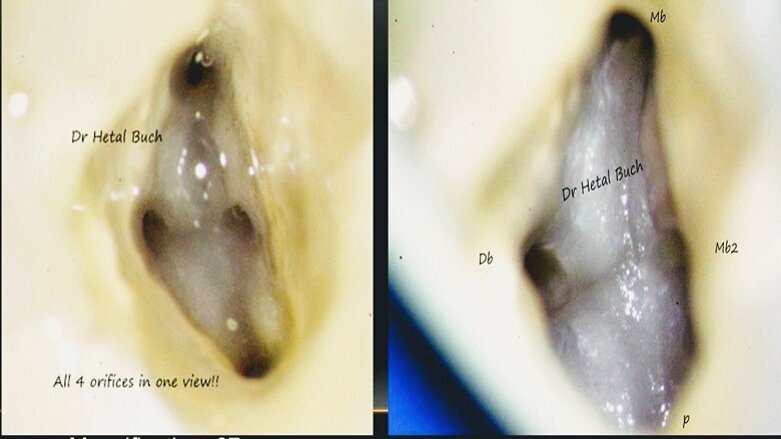

e.g. Higher magnification is needed for re-treatment Endodontics or for locating the elusive MB2, whereas, in cases of crown preps and periodontal treatment lower magnification will suffice. Steps of magnification varies according to the type of microscope and components used by the company.

Maxillary Molar Canals as sen under a microscope